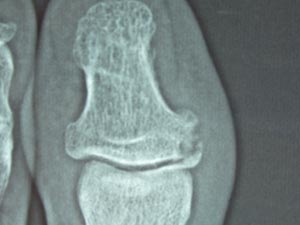

左足の第1指(おやゆび?)の先っちょの関節が壊れている。「何だろう、こんなの見たことがないなあ。」という有り難いコメント。

「違うと思うけど、もしかしたら腫瘍かも。」とのこと。